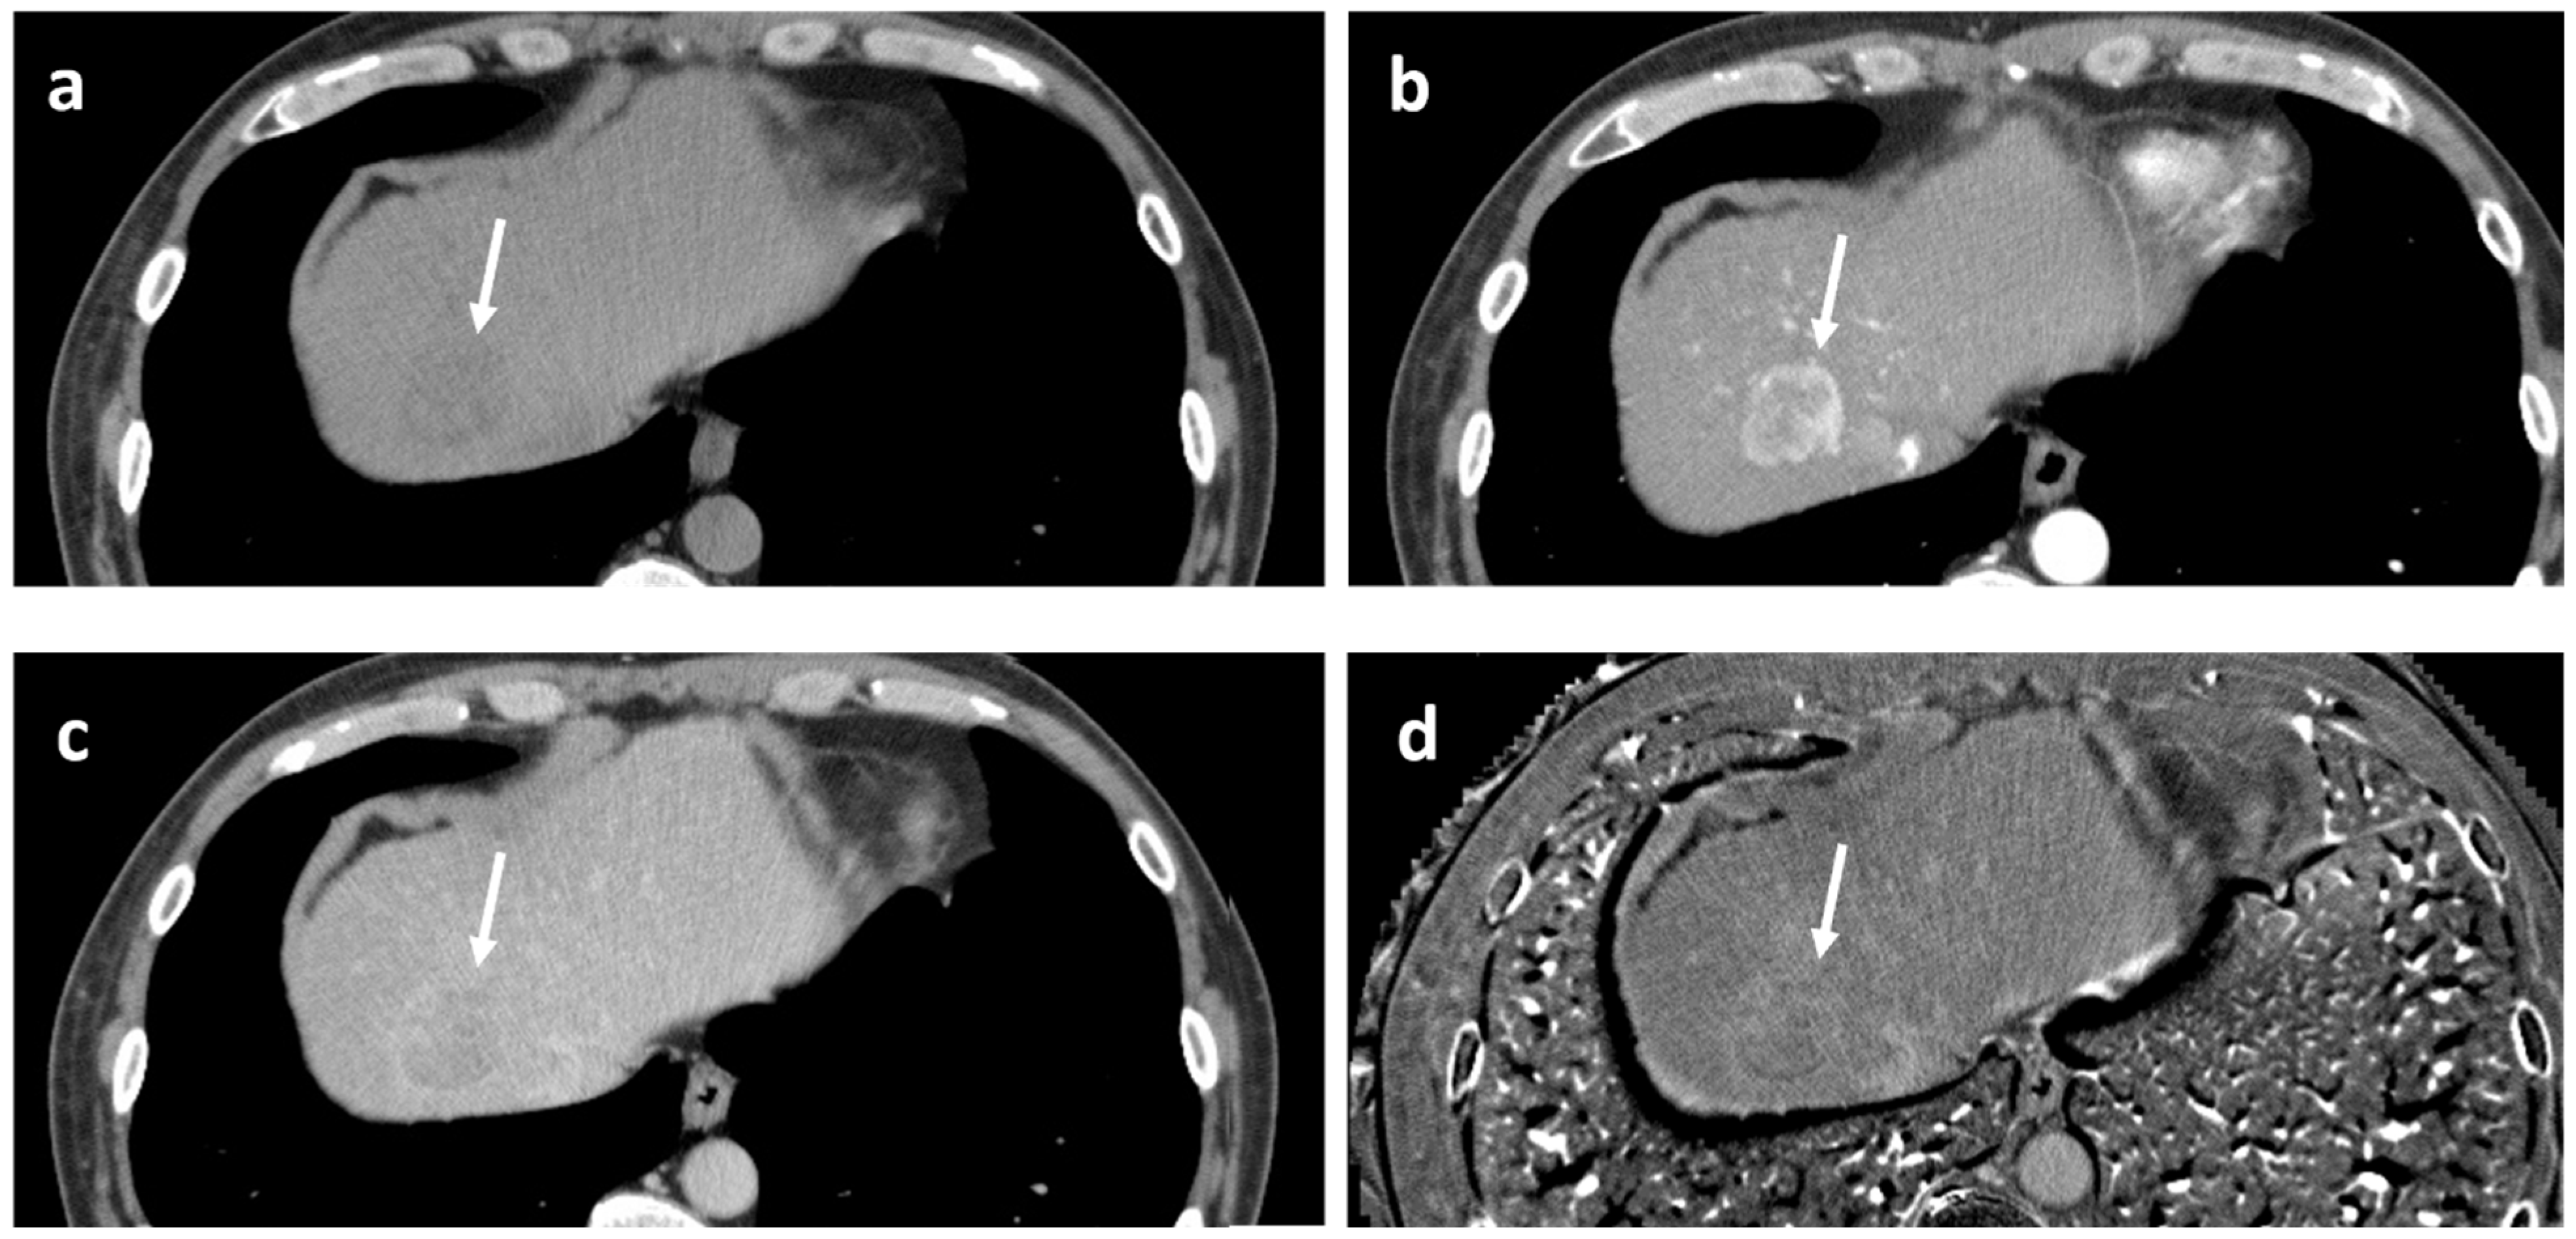

A representative washout positive case is shown in Figure 6.

Figure 6. Example of positive washout case at the equilibrium phase. 53-year-old man with alcoholic liver disease. Pathologically, moderately differentiated hepatocellular carcinoma of confluent multinodular type, without complete fibrous capsule, was confirmed. Fatty change and lymphocytic infiltration were observed within the tumor. (a) Precontrast CT. The tumor exhibits low density (arrow). Measured density were 46 and 56 Hounsfield units for the tumor and the background liver, respectively. (b) Arterial phase CT. The tumor shows periphery-dominant enhancement (arrow). (c) Equilibrium phase CT. The tumor exhibits apparent “washout” (arrow). (d) Extracellular volume fraction (ECV) map reveals slightly higher value of the tumor, as compared to the background liver. Measured ECVs were 38.5% and 33.1% for the tumor and the background liver, respectively. In this case, although the ECV of the tumor is slightly higher than that of the BGL, it was considered that the lower precontrast density of the tumor, possibly due to fatty change, contributed to the positive EqP washout.